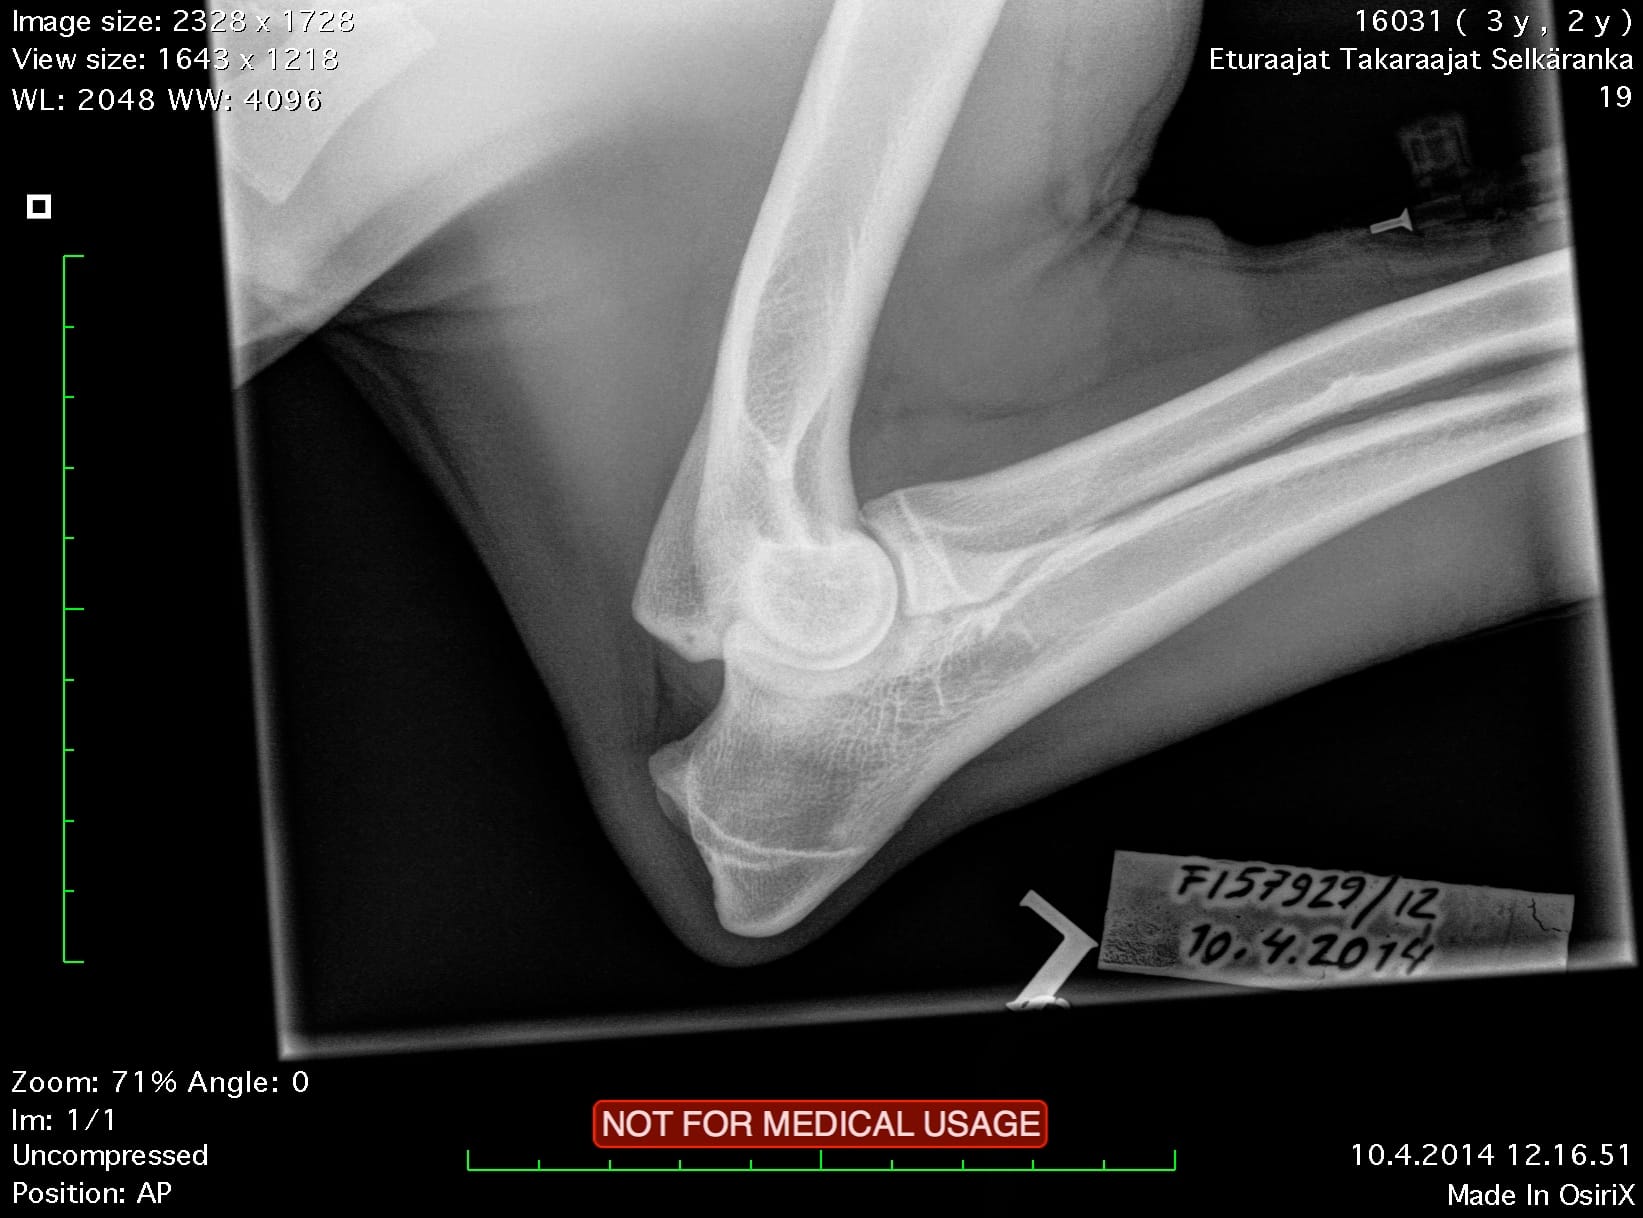

| Hips: | A/A | |

| Elbows: | 0/0 | |